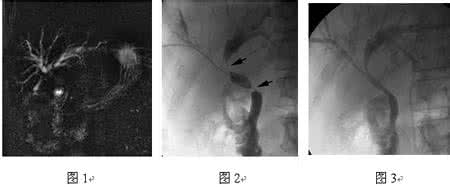

1.2 治疗方法 全部患者在DSA中给予局麻下行PTCD94例,“无痛”条件下36例。术前除常规准备外,要准备21G套管穿刺针、超滑导丝、超硬导丝、Cobra造影导管、多侧孔内外引流管、12-14F胆道内涵管、球囊扩张导管、支架等。穿刺点可根据个体不同情况选择经右腋中线8-9肋间、剑突下、经手术孔道等。根据病情进行外引流、内外引流、内涵管植入、内支架植入等。本组单纯外引流46例、内外引流31例、内涵管植入25例、支架植入18例。

术后无腹腔出血、胆汁瘘、腹膜炎、支架移位、胆汁胸腔瘘等严重并发症。胆道出血6例,经使用止血药物后12h后停止;12例逆行性感染,经抗生素、导泻药物应用,感染得以控制;8例出现术后引流管阻塞,行再次手术调整后,6例效果满意,2例仍引流不畅在1月后死亡。本组患者术后生存期最短的36天,最长的3年4个月,平均321天。112例术后7d总胆红素与直接胆红素降至术前50%以下,6例在调整引流管后10天降至术前50%以下,71例在术后30d降至正常,携管出院。全组在生存期内引流管再置换23例,支架再阻塞再植管引流9例。